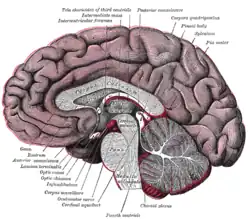

Hind- and mid-brains; posterolateral view Median sagittal section of brain

Median sagittal section of brain Nuclei of the pons and brainstem